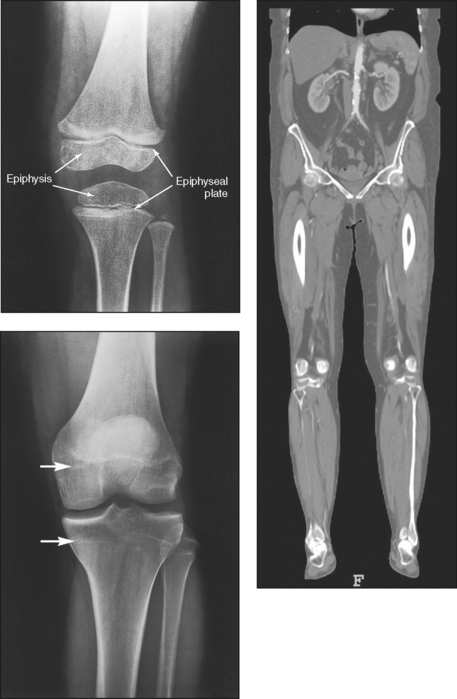

Secondary ossification occurs after birth when a separate bone begins to develop at both ends of each long bone. Each end is called the epiphysis (Fig. 3-15, B). At first, the diaphysis and epiphysis are distinctly separate. As growth occurs, a plate of cartilage called the epiphyseal plate develops between the two areas (Fig. 3-15, C). This plate is seen on long bone radiographs of all pediatric patients (Fig. 3-16, A). The epiphyseal plate is important radiographically because it is a common site of fractures in pediatric patients. Near age 21 years, full ossification occurs, and the two areas become completely joined; only a moderately visible epiphyseal line appears on the bone (Fig. 3-16, B).

Fig. 3-16 A, Radiograph of a 6-year-old child. Epiphysis and epiphyseal plate shown on knee radiograph (arrows). B, Radiograph of same area in a 21-year-old adult. Full ossification has occurred, and only subtle epiphyseal lines are seen (arrows). C, PA radiograph of hand of a 2½-year-old child. Note early stages of ossification in epiphyses at proximal ends of phalanges and first metacarpal, distal ends of other metacarpals, and radius. (C, From Standring S: Gray’s anatomy, ed 40, New York, 2009, Churchill Livingstone.) Churchill Livingstone